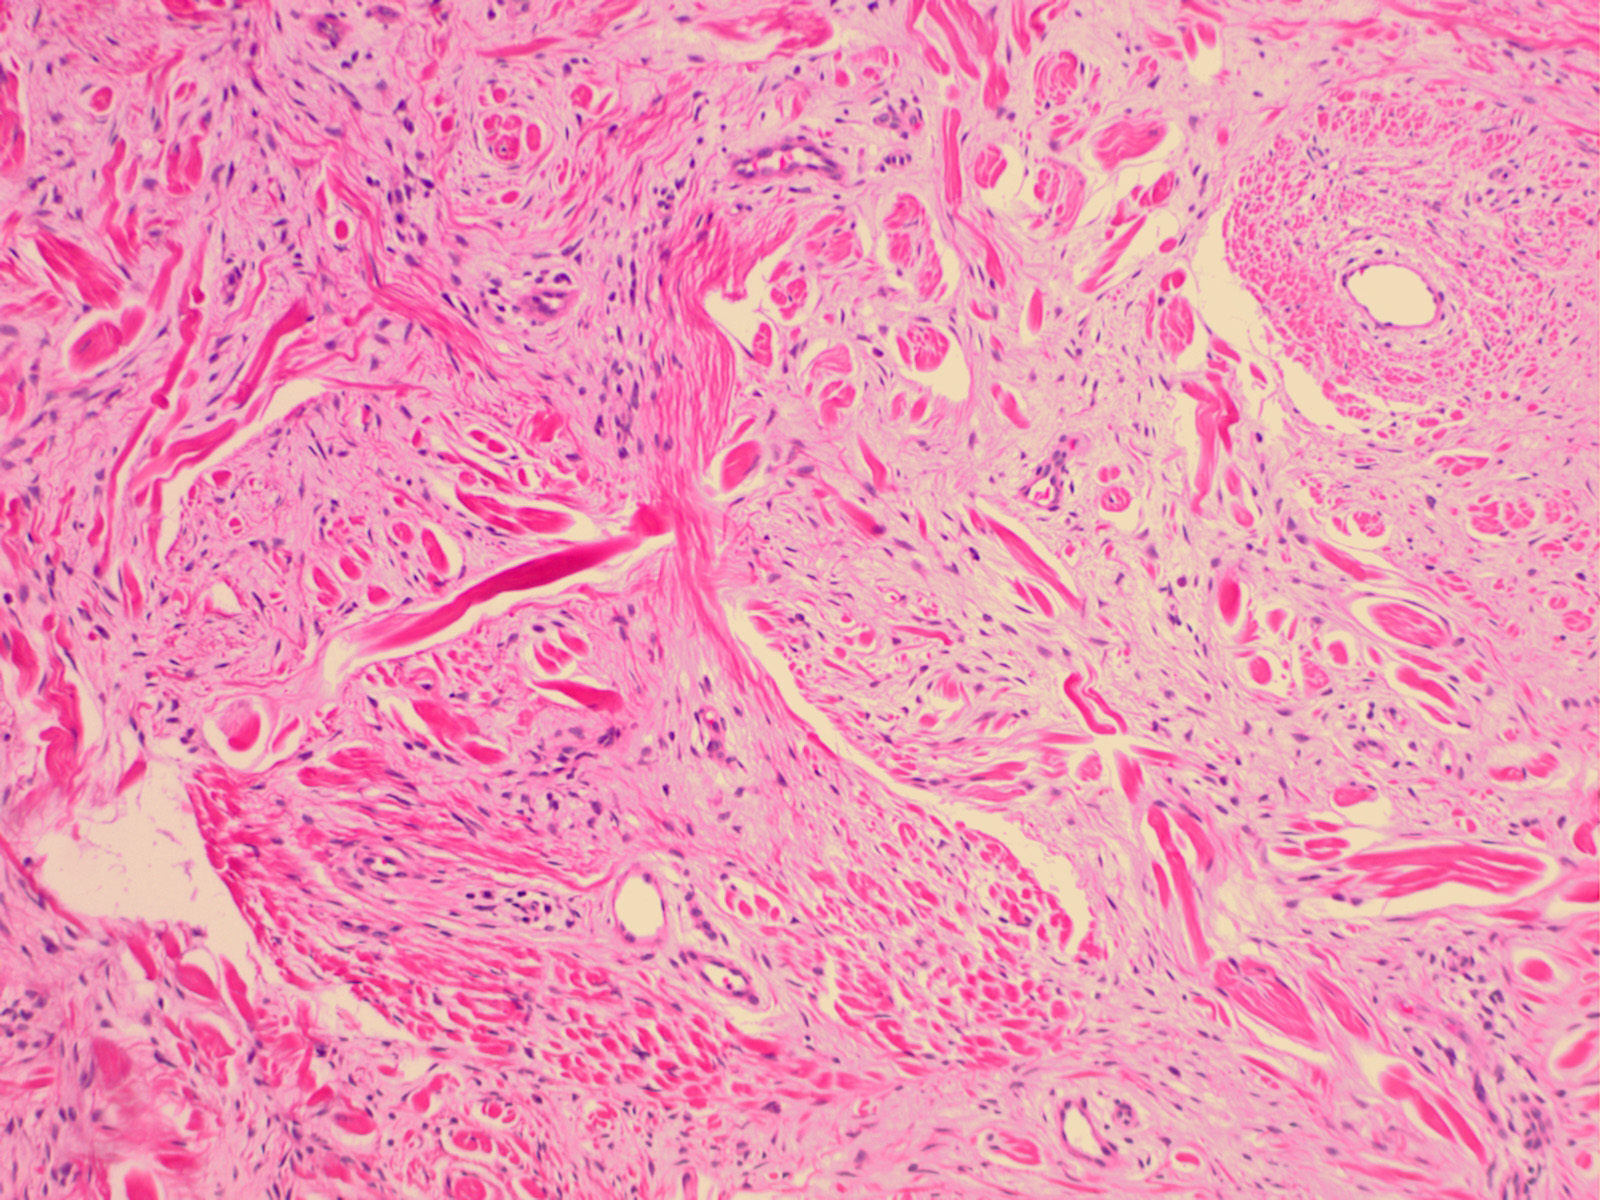

Superficial acral fibromyxoma = الورم المخاطي الليفي السطحي في النهايات